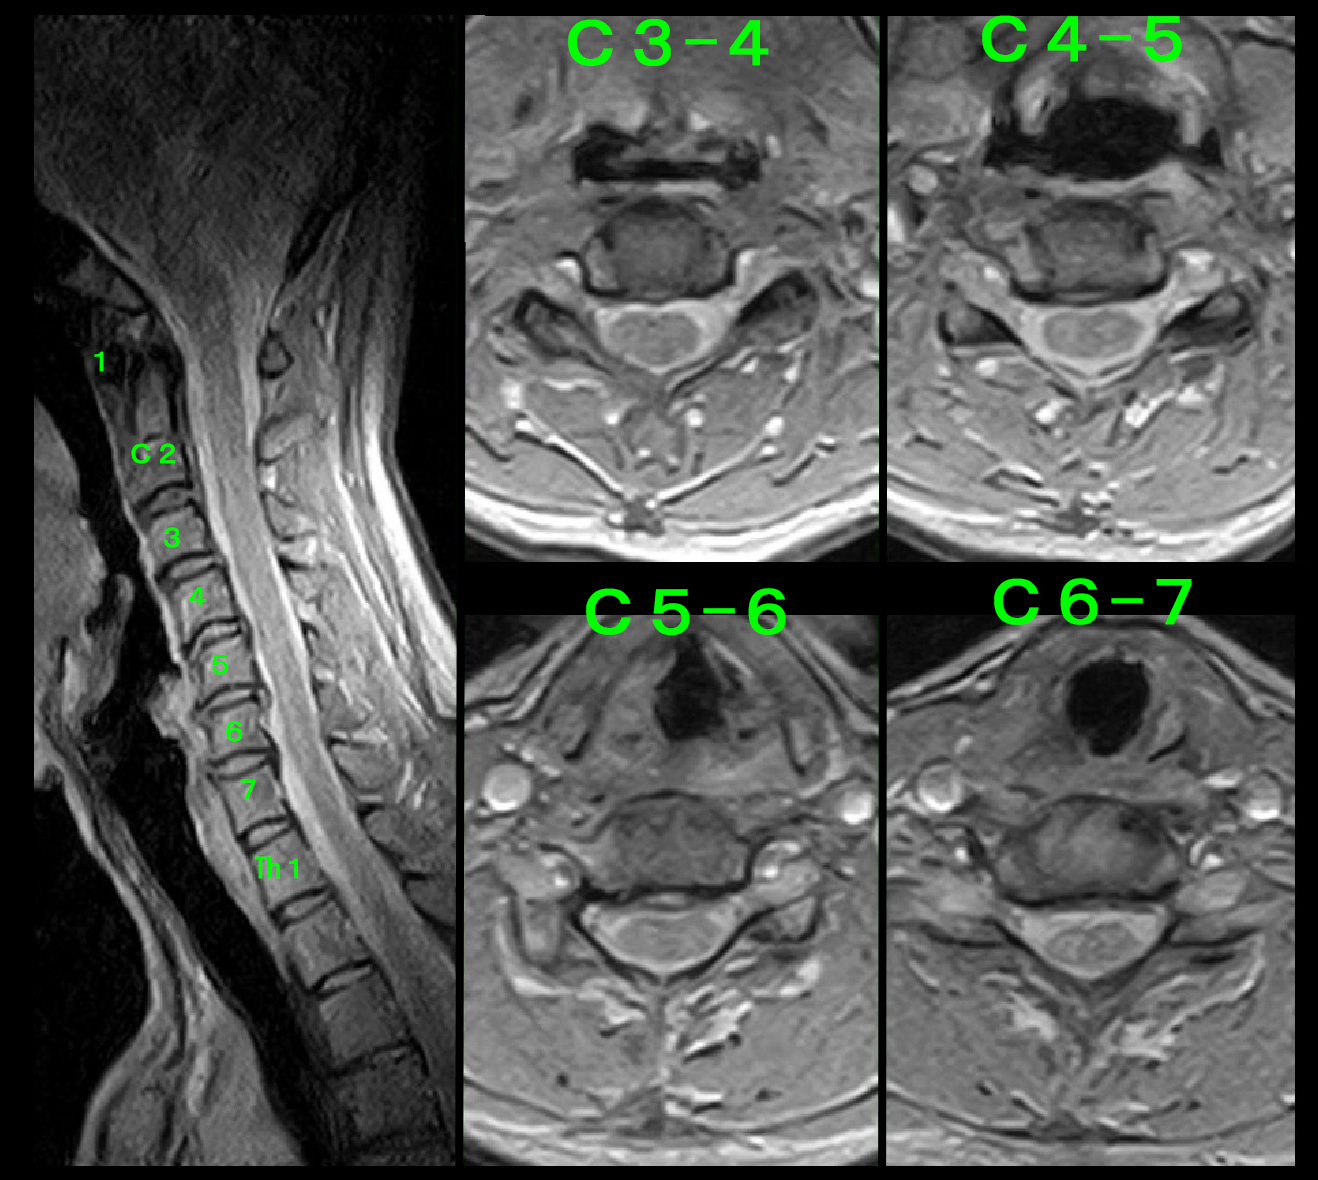

50才女 MR2.jpg

C3-4に軽度の、C4-5に軽度~中等度の、C5-6に中等度の椎間板ヘルニアを確認しました。1週間の服薬でも頚部痛はVAS7~8のままであるとのことでした。通常はこの頚椎のMRI所見であればノイロトロピンとプレドニゾロンの服薬である程度は症状の軽減はえられるはずと考えます。そのため同処方を3週継続しました。

お正月をはさみ、3週服薬経過した1月17日の時点でも頚部痛は不変でVAS6~8(6はけっこう痛い、8はとても痛い)とのことで、目の奥や耳の奥に痛みを感じるとのことでした。この時点でこの患者さんの頚部痛は通常の痛みではなく、慢性痛であると判断し、ノイロトロピンとアナフラニールという慢性痛に効果が期待できる抗うつ薬を処方しました。(当院ホームページの資料や動画で学ぶの “痛みについて その2 治療の困難な慢性痛について” を参照してください。)